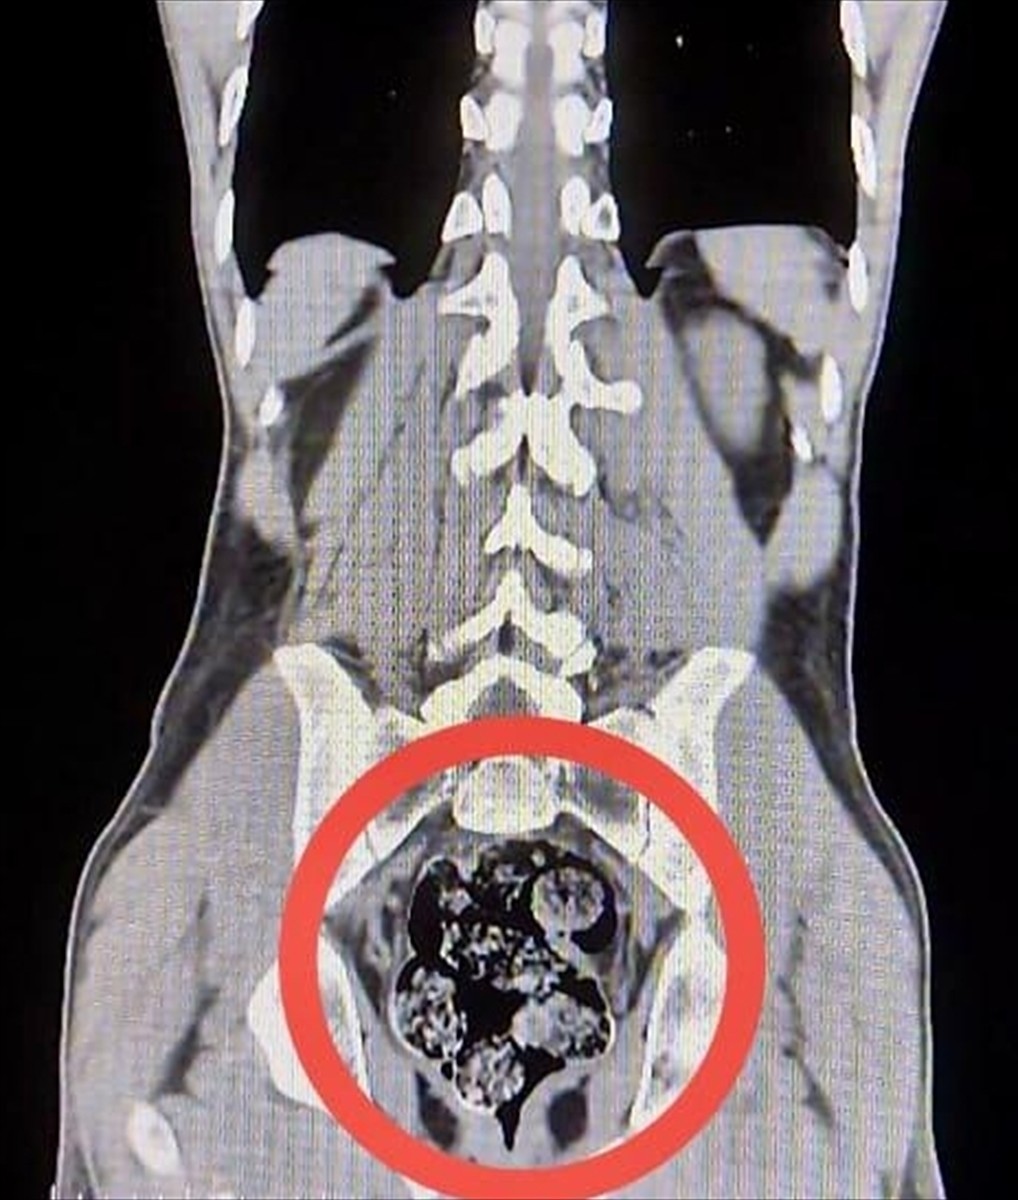

Gözaltına alınan zanlılar, Harakani Devlet Hastanesi'ne sevk edildi. Burada yapılan incelemelerde, Amır Rafıeı S'nin mide ve bağırsaklarında 7 parça halinde toplam 203,02 gram sentetik uyuşturucu tespit edildi.

Cerrahi müdahaleyle çıkarılan uyuşturucu maddelerinin ardından, her iki zanlı adliyeye sevk edildi ve "uyuşturucu veya uyarıcı madde imal ve ticareti yapmak" suçundan tutuklandı.